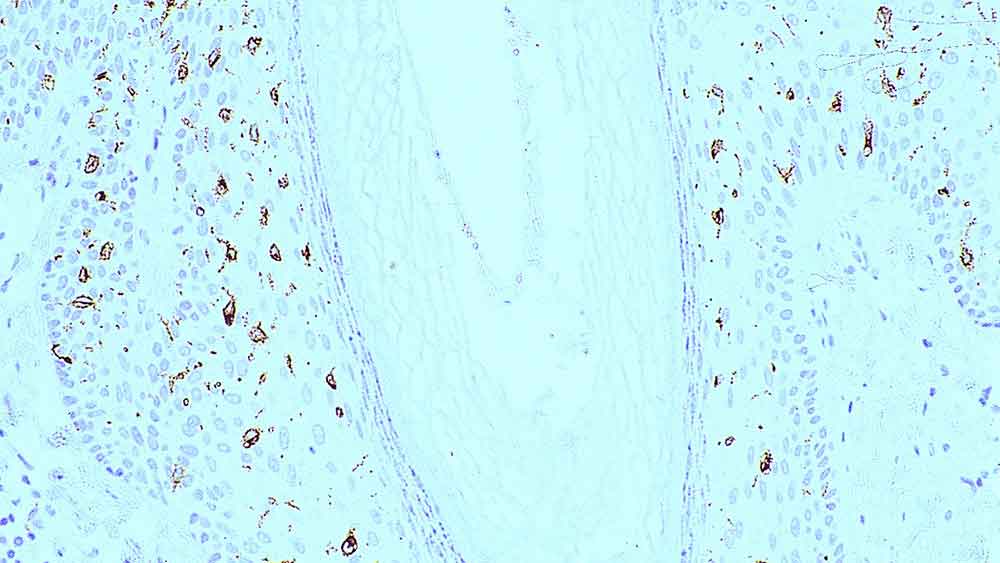

IHC-P analysis of human skin tissue using GTX01915 Langerin antibody [12D6].